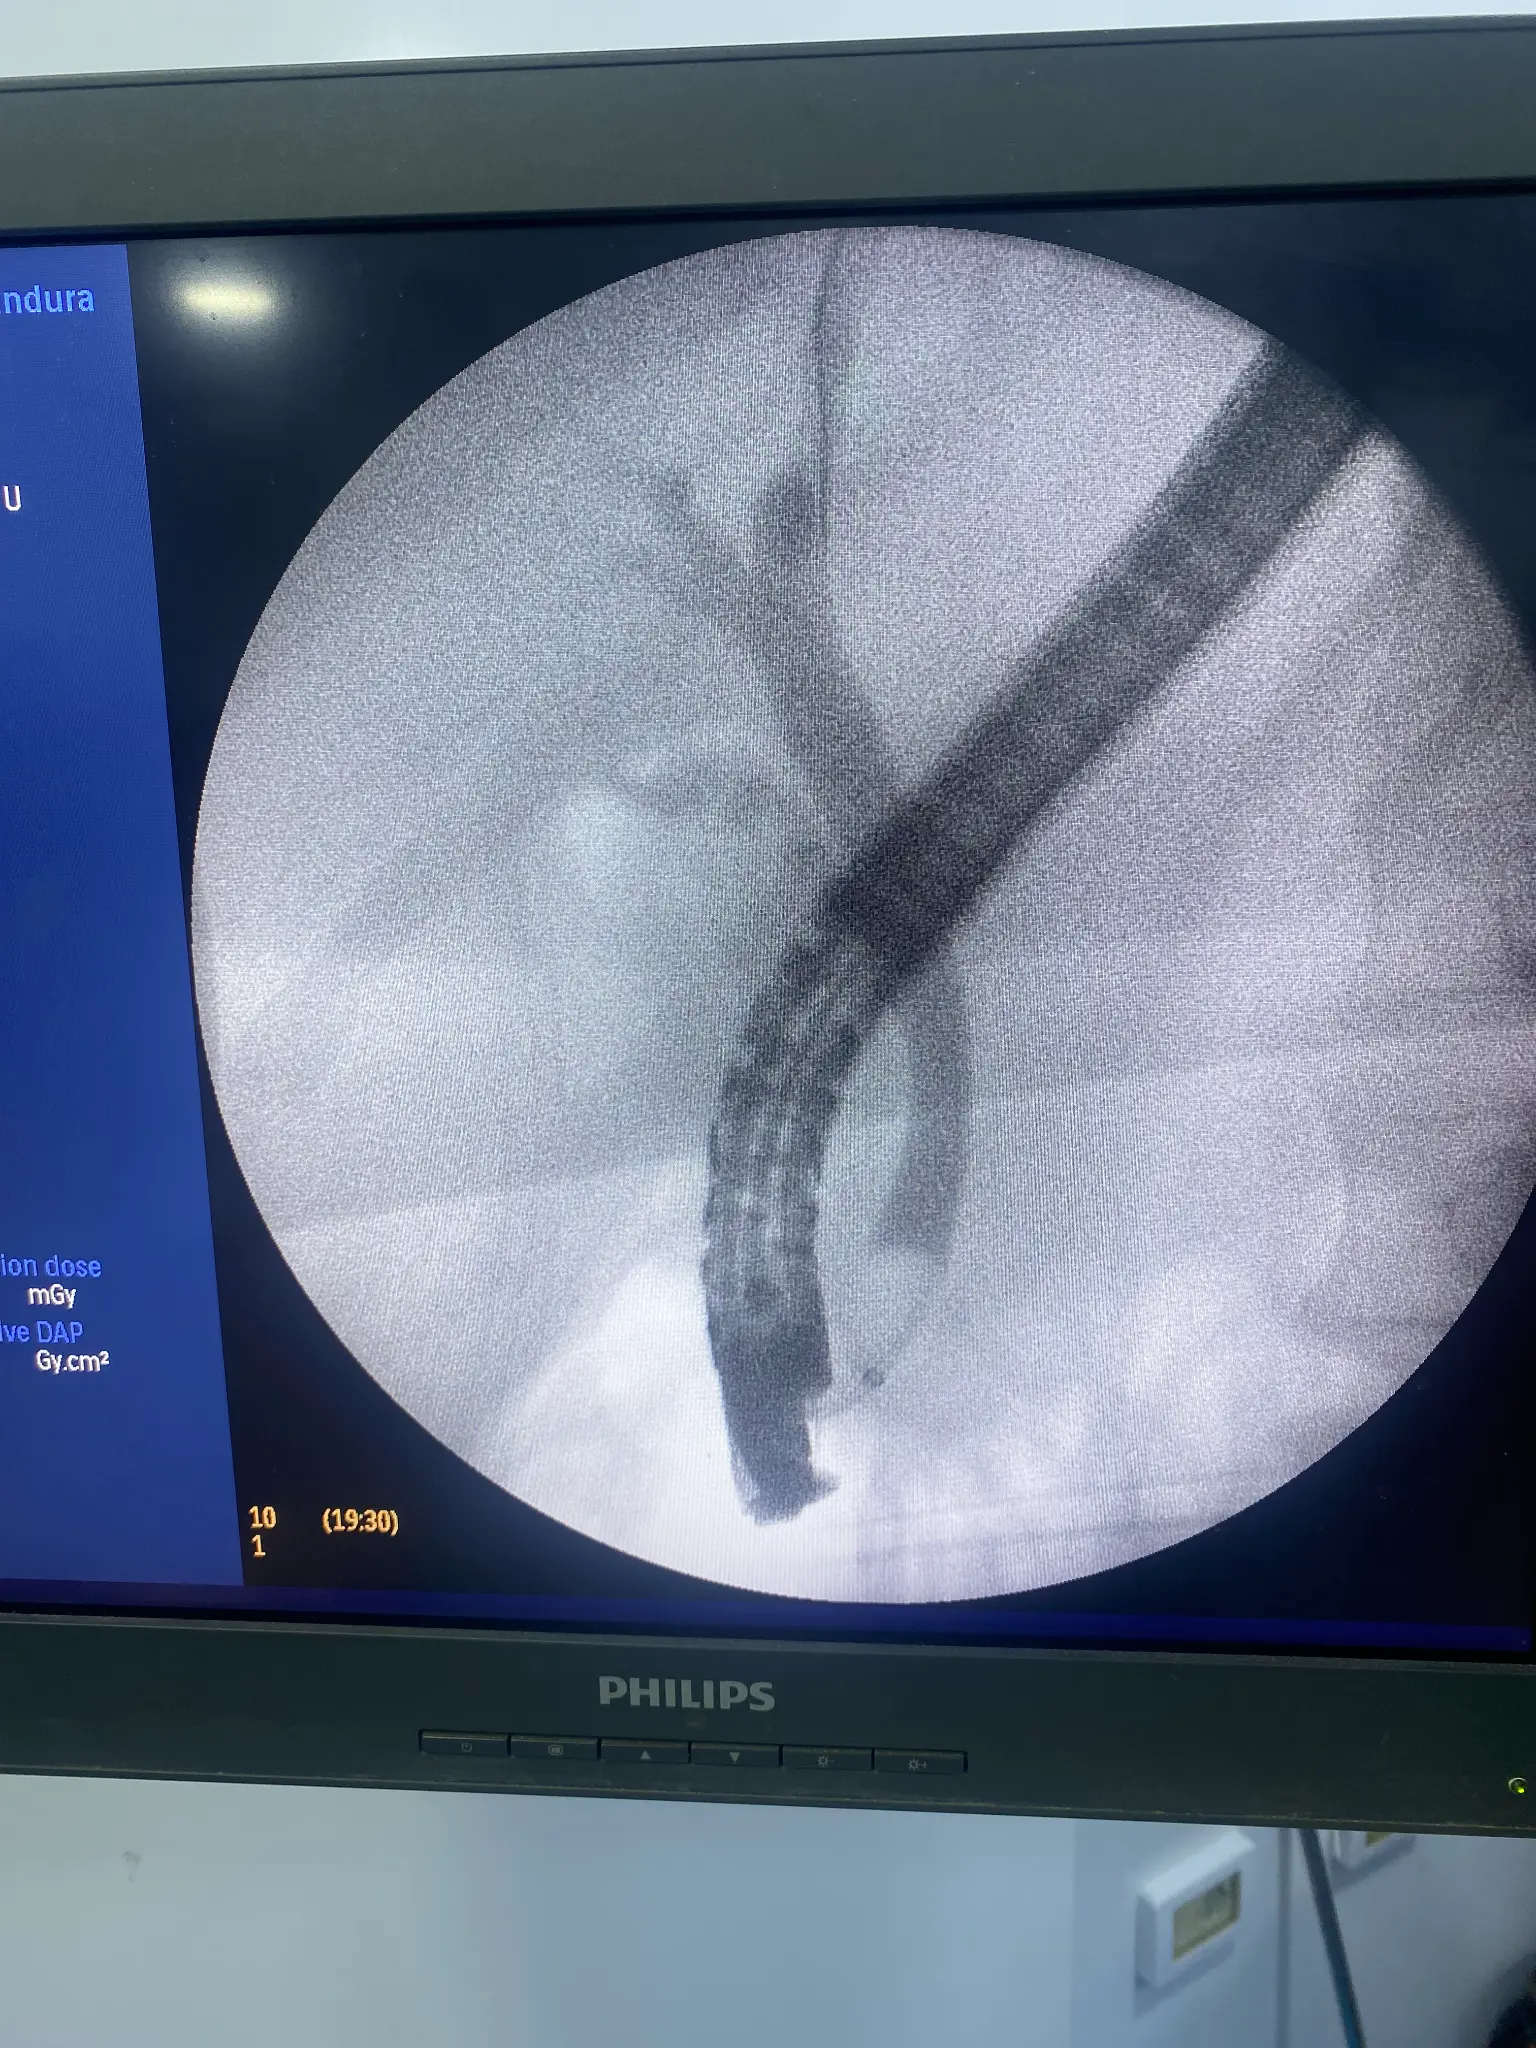

ERCP Intervention Photos

Removal of bile duct stones using specialized baskets or balloons. Larger stones may be fragmented using mechanical lithotripsy or laser techniques before extraction.

Cutting the sphincter of Oddi muscle to widen the bile duct opening, facilitating stone removal and improving bile drainage. This is often the first step in therapeutic ERCP.